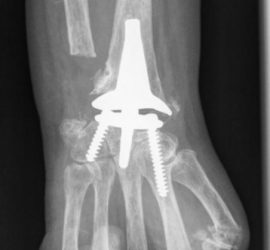

A prótese Total do Punho no Congresso Hispano-Luso de Cirurgia da Mão

Apresentou uma Palestra intitulada “A nossa experiencia com A prótese Total do Punho ” Congresso Espanhol e Hispano-Luso de Cirurgia da Mão, que se realizou em Marbella nos dias 5 a 7 de Abril de 2017. A sua intervenção foi baseada na Casuística da Unidade de Cirurgia da Mão do Hospital Stº […]

Prótese Total do punho no Hospital da Parede, Cascais

Desde há 12 Anos, A Unidade de Cirurgia da Mão do Hospital de Santo António, tem vindo com regularidade, a efectuar este procedimento cirútgico. Progressivamente, outros Centros de Cirurgia da Mão Portugueses têm vindo a escolher este método para tratamento dos seus Pacientes. A convite dos Colegas Ortopedistas da Unidade […]

Palestra: A Prótese Total do Punho no 24º Congresso Português de Cirurgia da Mão

O 24º Congresso Português de Cirurgia da Mão irá realizar-se em Peniche nos próximos dias 23 e 24 de Setembro de 2016. Será constituído por duas Mesas Redondas versadas aos Temas: 1 – Mão Queimada 2 – Artroplastias do Punho Contará com várias Conferencias proferidas por Colegas Portugueses e […]

Palestrante convidado para integrar Mesa Redonda sobre Complicações das Artroplastias do Membro Superior. Na sua palestra apresentou as complicações das Artroplastias do punho. Fez uma Revisão da Bibliografia Internacional e comentou as Complicações ocorridasl, baseadas na sua experiencia com mais de nove anos de com as próteses totais do Punho.

Artroplastias de la Muñeca no 49º Congreso Sociedade Española de Cirurgia Ortopedica y Traumatóloga – Málaga, Espanha 3-5 outubro de 2012

Palestrante convidado pela Sociedade Espanhola de Cirurgia Ortopédica e Traumatológica para proferir uma apresentação versada ao tema da Artroplastia Total do Punho. A palestra esteve inserida numa mesa-redonda sobre Artroplastia do Membro Superior e nela foi exposta a experiência pessoal sobre a Protese Total do Punho.